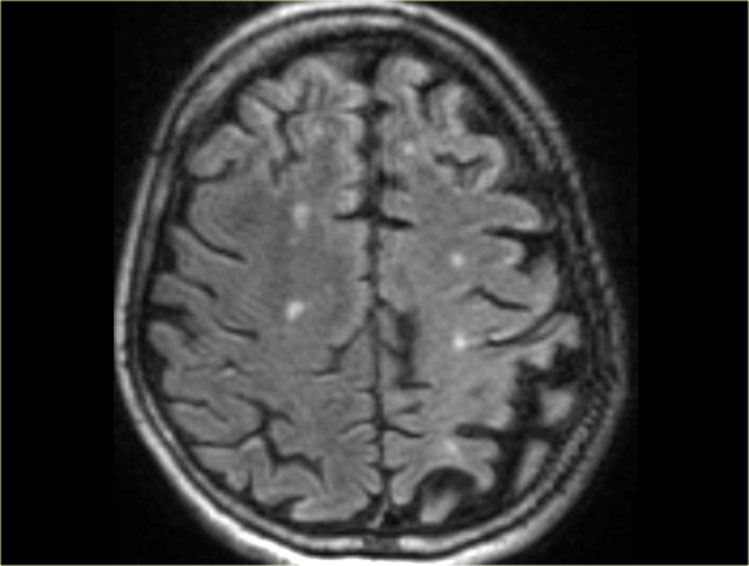

Mri Scan Of Brain With Multiple Sclerosis Photograph By Dr Crum

www.lupon.gov.ph

www.lupon.gov.ph

Representative Brain MRI Of Dementia Patients. A Patient A Was

Pin On B R A I N I M A G E S

www.pinterest.com

www.pinterest.com

brain matter mri white disease imaging dementia alzheimer scan vascular hyperintensities normal magnetic resonance alzheimers hyperintensity t2 google intensities bmj